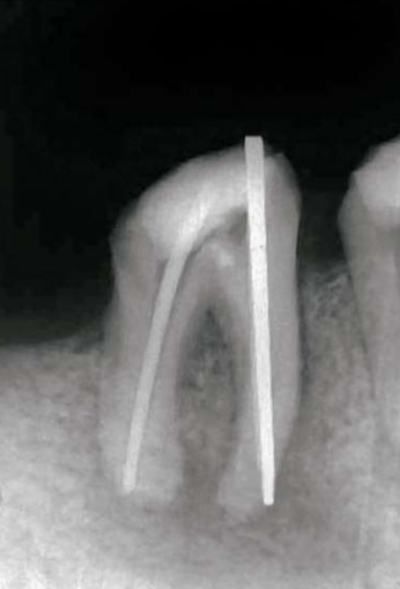

65 歳の男性。下顎右側第一大臼歯部歯肉の腫脹を主訴として紹介により来院した。6か月前に同部の治療を受けたが、2週前から歯肉が腫脹したという。再根管治療を行うこととし、根管を確認するためポイントを挿入してエックス線検査を行った。検査時のエックス線画像を別に示す。

最も疑われるのはどれか。1つ選べ。

a. 穿 孔

b. 器具破折

c. 歯根破折

d. 側枝の存在

e. レッジの形成